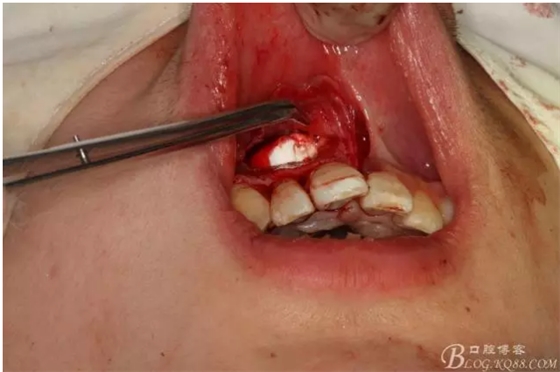

圖6.超聲骨刀切除根尖3mm。